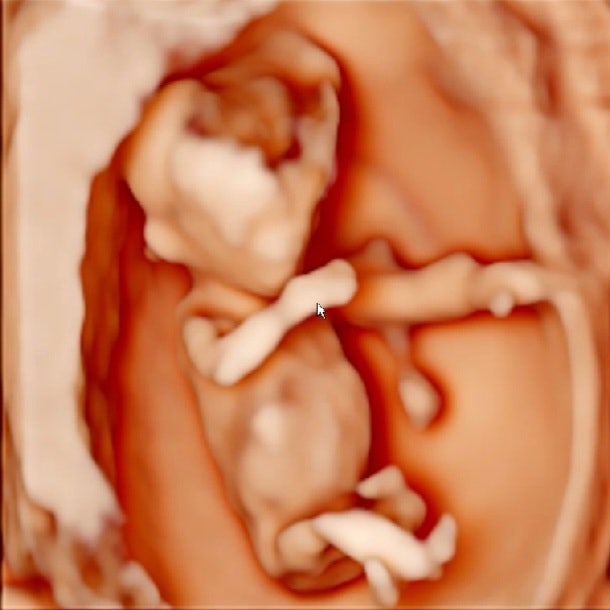

임신 12주차, 다양한 검사가 기다리고 있었다. NT (목 투명대 두께) 확인 입체초음파 보기 기형아 검사 ...

8주차는 임신 기간 중 태아의 가장 귀여운 모습을 볼 수 있는 시기다. 젤리곰❤️ 얼마나 귀엽겠냐 라는 생...